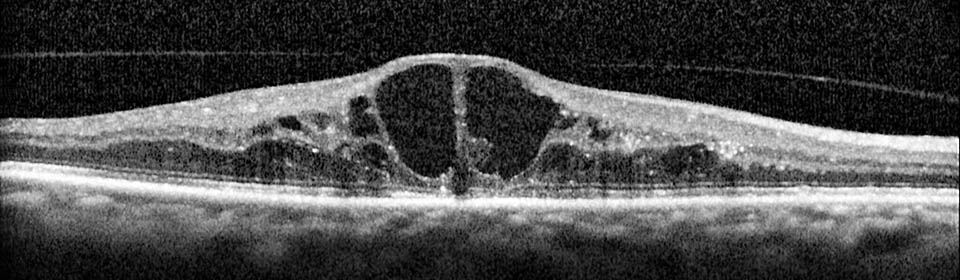

Almost 1 in 10 diabetics has sight threatening retinopathy.

Diabetes is the leading cause of blindness in the 25 to 75 age group.